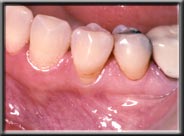

Some people are born without sufficient attached gingiva to prevent the muscle in the alveolar mucosa from pulling the gum down. In these cases the gum slowly continues to recede over time, even though the patient may be very conscientious with their oral health. This is not an infection, as is seen with periodontal disease, but rather simply an anatomic condition. Unfortunately, bone recession is occurring at the same time the gum is receding. This is because the bone, which is just under the gum, will not allow itself to become exposed to the oral cavity and moves down with the gum.

With the wear and tear of time, even normal attached gum can be worn away, generally from vigorous brushing. This often happens in people with naturally thin tissues, or when the tissues have been stretched during orthodontics. If there is still adequate attached gum to act as a barrier to the muscle, the treatment for recession is to ensure further damage isn't done when brushing. However, if the attached gum is worn to the point where it cannot resist the constant pull of the mucosa, recession will continue unless a new hard band of gum is placed. Unchecked, the recession can cause tooth loss as the bone recedes with the tissue and tooth support weakens.